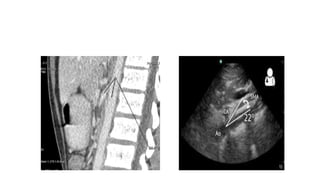

CT

• CT is often initial investigation performed for the evaluation of

suspected bowel pathology.

• CT reveals thickening of ileocecal valve

• Medial wall of caecum is disproportionately thickened and often

associated with soft tissue mass that engulfs the terminal ileum.

CT/MRI

• Enables visualization of vascular compression of duodenum and

measurement of aortomesentric distance and angle.

• Normally aortomesentric angle is 25-60 degree and aortomesentric

distance is 10-28 mm

• In SMA syndrome both parameters are reduced with values of 6-15

degree and 2-8 mm.